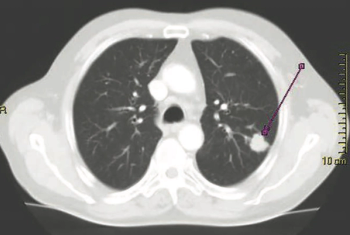

2019 World Conference Of Lung Cancer Round-Up

Five notable abstracts from the 2019 World Conference on Lung Cancer (WCLC).